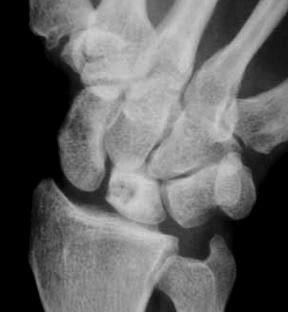

Diagnosis? Etiology?

Keinbochs

Imaging to help define collapse of lunate